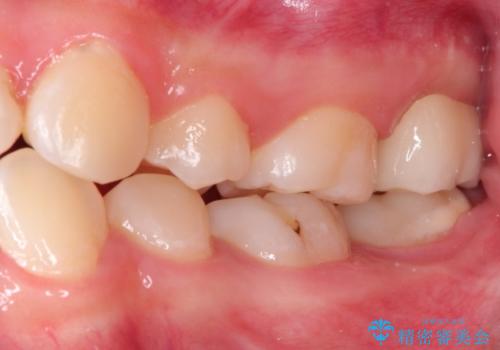

奥歯が痛い。ラバーダム使った治療がしたい。

- 他院にて奥歯の治療をしても痛みが引かずに、ラバーダムの存在を知り、無菌的な治療を行える病院を探して当院を受診されました。

根管治療~フルジルコニアクラウンにて修復しております。

治療前には打診、圧痛がありましたが治療後には症状が消失し、3ヶ月後のレントゲンでも透過像の縮小を認めています。

治療介入時、根管内部にはカリエスや異物が存在する状態でしたが適切な処置を行うことで症状を改善することができました。